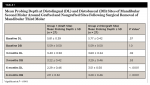

At 3 months post-treatment, pocket depths were measured for both cases and controls at distobuccal and distolingual sites of the 2Ms. Mean pocket depth distolingually was 3.40 mm at grafted sites and 3.60 mm at nongrafted sites. At the distobuccal aspect the mean pocket depth was found to be 3.22 mm at grafted sites and 3.29 mm at nongrafted sites. Grafted sites showed better results for decrease in pocket depth especially in the distolingual aspect; however, the results were not statistically significant (P = .0213) (Table 1). The decrease in the mean pocket depth distobuccally was better in the grafted site but not statistically significant (P = .5372).

After 6 months, mean pocket depth distolingually was 2.29 mm at grafted sites and 3.51 mm at nongrafted sites. At the distobuccal aspect the mean pocket depth was found to be 2.11 mm at grafted sites and 3.29 mm at nongrafted sites. Grafted sites showed better results in comparison to the nongrafted sites in both the distolingual and distobuccal aspects with statistically significant results (P < .0001) (Table 1).

The association of grafting with the presence of dentin hypersensitivity in relation to 2Ms post 3M surgery showed that at 3 months 19% (n = 5) of grafted sites had dentin hypersensitivity versus 63% (n = 17) in nongrafted sites. At 6 months, none of the grafted sites had dentin hypersensitivity compared with 48% (n = 13) of nongrafted sites. This indicates that grafting is associated with reduced dentin hypersensitivity in 2Ms, which was statistically significant at 3 months (P = .002) and 6 months (P = .0001) (Table 2 and Table 3).